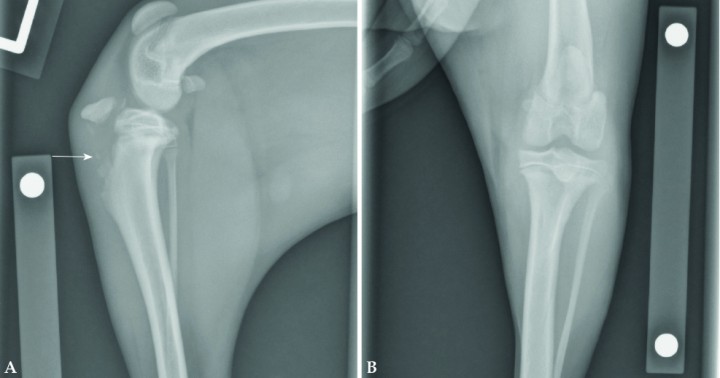

<p>Radiografías de codo en un cachorro de 3 meses de edad. En la proyección mediolateral (Fig. 6A) podría resultar difícil diagnosticar la fractura, aunque se aprecian elementos que deberían generar sospecha de que no es normal, como la presencia de un posible fragmento óseo superpuesto con la cortical caudal del húmero distal (flecha). Si el estudio radiológico no se completa con una proyección craneocaudal (Fig. 6B) es posible cometer el error de no diagnosticar esta fractura Salter-Harris de tipo IV de la parte lateral del cóndilo humeral.</p>

Radiografías de codo en un cachorro de 3 meses de edad. En la proyección mediolateral (Fig. 6A) podría resultar difícil diagnosticar la fractura, aunque se aprecian elementos que deberían generar sospecha de que no es normal, como la presencia de un posible fragmento óseo superpuesto con la cortical caudal del húmero distal (flecha). Si el estudio radiológico no se completa con una proyección craneocaudal (Fig. 6B) es posible cometer el error de no diagnosticar esta fractura Salter-Harris de tipo IV de la parte lateral del cóndilo humeral.